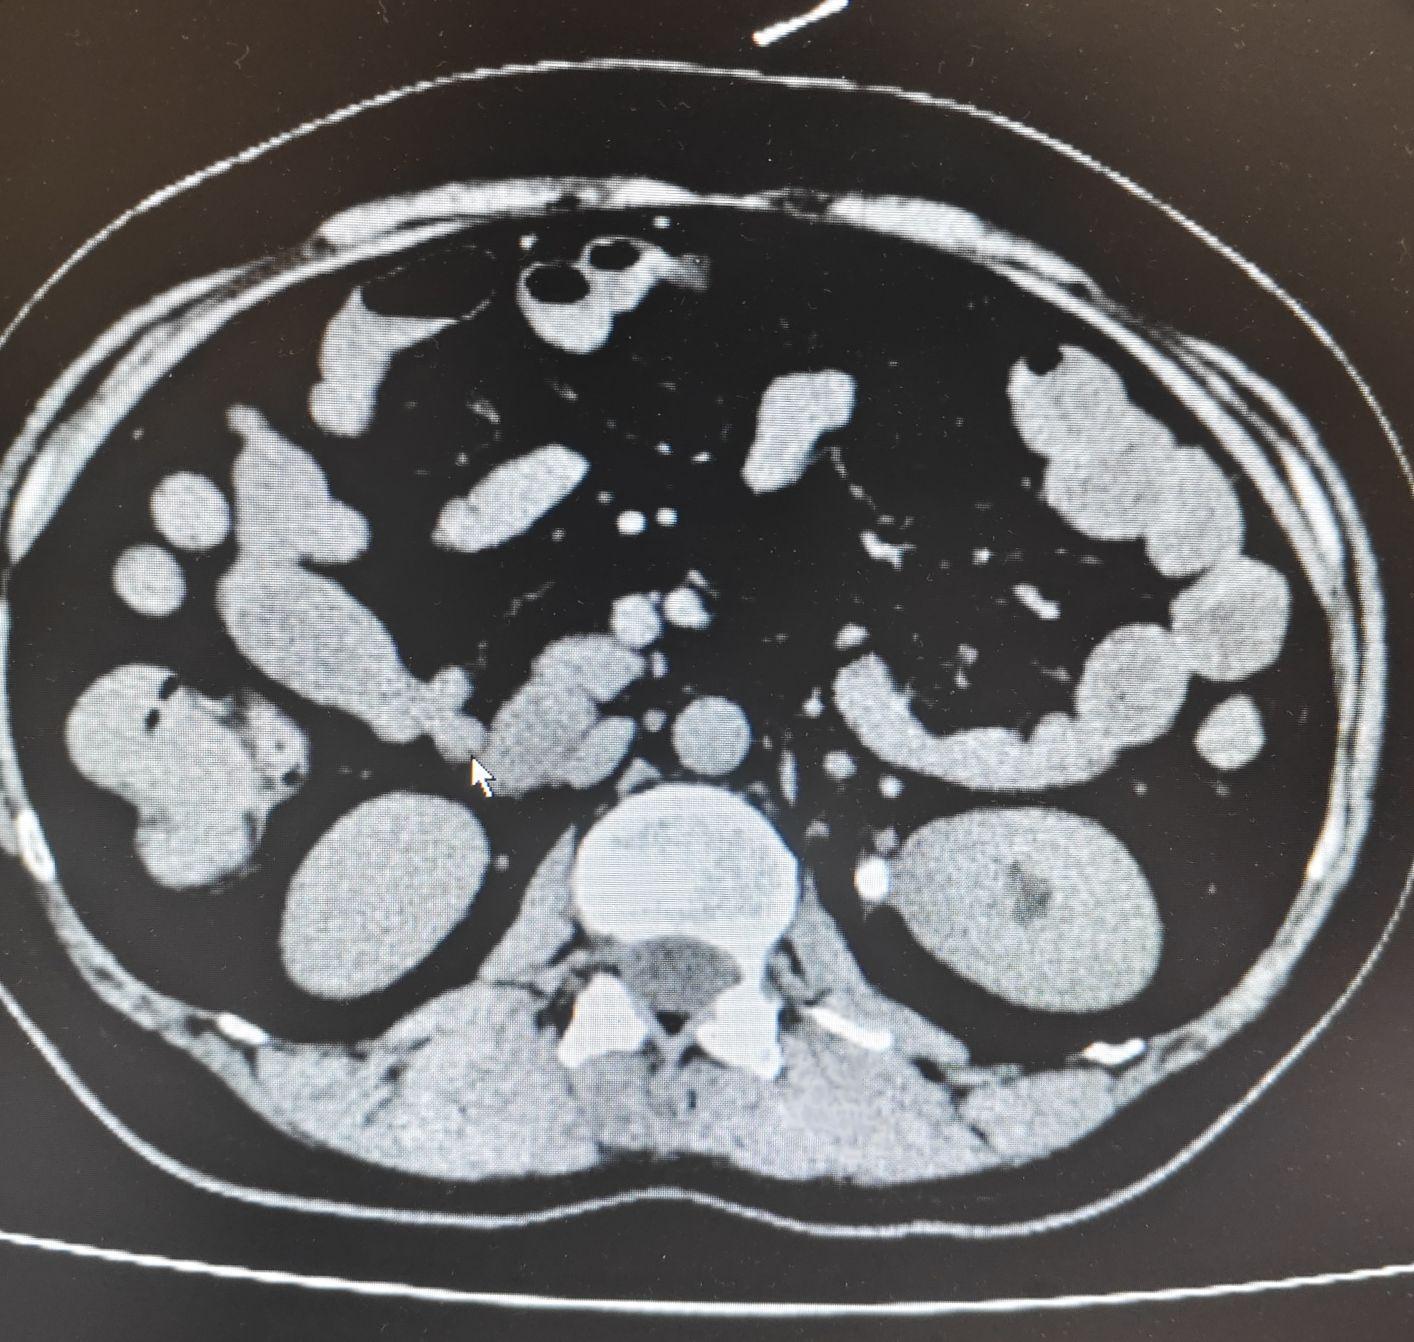

下腹部+盆腔CT(我院急诊,2026-1-30)左肾盂输尿管移行处结石,左肾盂肾盏轻度扩张,伴左输尿管上段及左肾周围少许渗出,左肾略大、密度略减低,肾周筋膜略增厚。左肾盏内点状结石;血分析+全程C-反应蛋白白细胞(9-HR):14.07×10^9/L,超敏C反应蛋白:>10.00mg/L,C-反应蛋白:10.57mg/L↑;尿液分析*白细胞(9-HR):25(1+)cells/μL;复查下腹部CT平扫+盆腔CT平扫+薄层(2026-2-2)左侧肾盂、输尿管移行处结石,以上肾盂肾盏扩张;左肾盏点状结石。右侧输尿管下段走行区近膀胱入口处点状致密影,结石可能。不均匀脂肪肝;肝内多发囊性病变。泌尿系(女)(含肾、输尿管、膀胱)彩超左肾小结石。右肾、膀胱声像图未见明显异常。双侧输尿管未见明显扩张。

1.患者中年女性以间歇性左侧腰腹部疼痛3天,加重3小时之主诉入院。2.专科情况双肾区无隆起,肾下极未触及,左侧肾区压痛阴性、叩痛阴性,左侧肾区压痛阴性、叩痛阴性,左侧输尿管走行区压阳阴性,耻骨上区压痛阴性,叩诊鼓音。尿道外口无红肿及异常分泌物。3.辅助检查下腹部+盆腔CT(我院急诊,2026-1-30)示左肾盂输尿管移行处结石,左肾盂肾盏轻度扩张,伴左输尿管上段及左肾周围少许渗出,左肾略大、密度略减低,肾周筋膜略增厚。左肾盏内点状结石;血分析+全程C-反应蛋白示白细胞(9-HR):14.07×10^9/L,超敏C反应蛋白:>10.00mg/L,C-反应蛋白:10.57mg/L↑;尿液分析示白细胞(9-HR):25(1+)cells/μL。